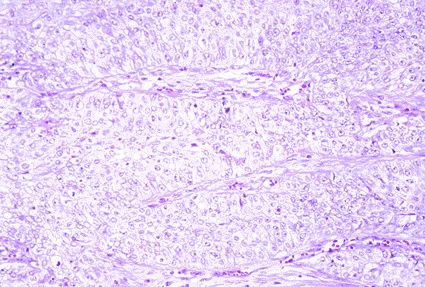

HNPCCにおける腎盂癌の病理組織像 ID:70の腫瘍の部分を拡大した写真です。移行上皮癌の組織学的所見が認められます。なお、この例では固有筋層へ浸潤しておりませんでした。

疾患(病理主体)の分類悪性上皮性腫瘍/その他

部位(臓器別)その他/

検査方法ミクロ